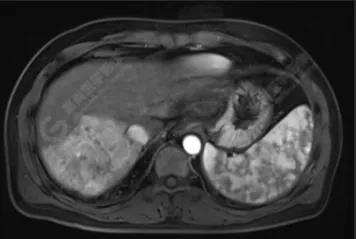

經(jīng)與放射科協(xié)調(diào),當(dāng)天即為該男士安排了上腹部磁共振平掃+增強(qiáng)檢查。

檢查結(jié)果如下:

肝硬化、原發(fā)性肝癌

1.肝硬化

原發(fā)性肝癌指原發(fā)于肝細(xì)胞或肝內(nèi)膽管上皮細(xì)胞的惡性腫瘤,是目前我國第4位常見惡性腫瘤及第2位腫瘤致死病因,主要包括肝細(xì)胞癌(HCC)、肝內(nèi)膽管癌(ICC)和HCC-ICC混合型3種不同病理學(xué)類型,3者在發(fā)病機(jī)制、生物學(xué)行為、組織學(xué)形態(tài)、治療方法以及預(yù)后等方面差異較大,其中HCC占85%~90%。